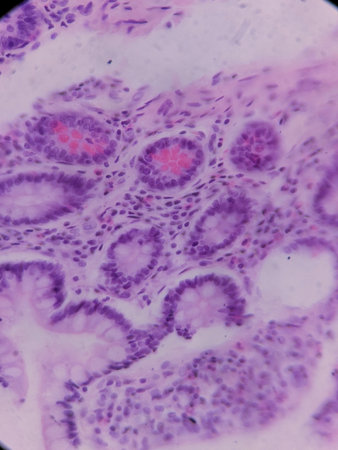

Ovarian cancer, light micrograph, photo under microscope. Photograph shows a fragment of a cancerous tumor in the female ovary. Selective focus